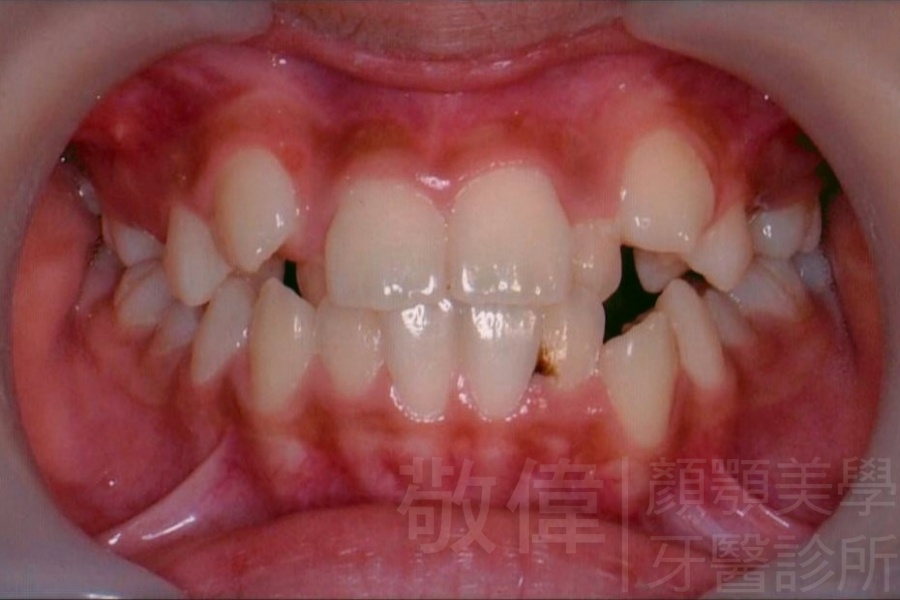

| 9 | 前牙美容 | 矯正+美容晶瓷貼片 | ||